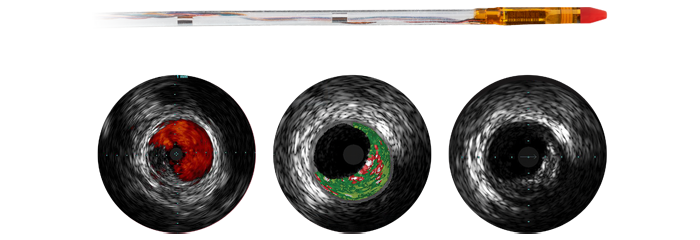

The Eagle Eye Platinum digital IVUS catheter is the #1 choice of physicians for intravascular imaging (in the US).* As a unique plug-and-play intravascular imaging catheter it is designed for ease of use and deliverability. Features include a soft tapered tip, GlyDx hydrophilic coating for increased lubricity, a long, rapid exchange lumen for improved pushability, three radiopaque markers, and compatibility with SyncVision for co-registration with angiography.